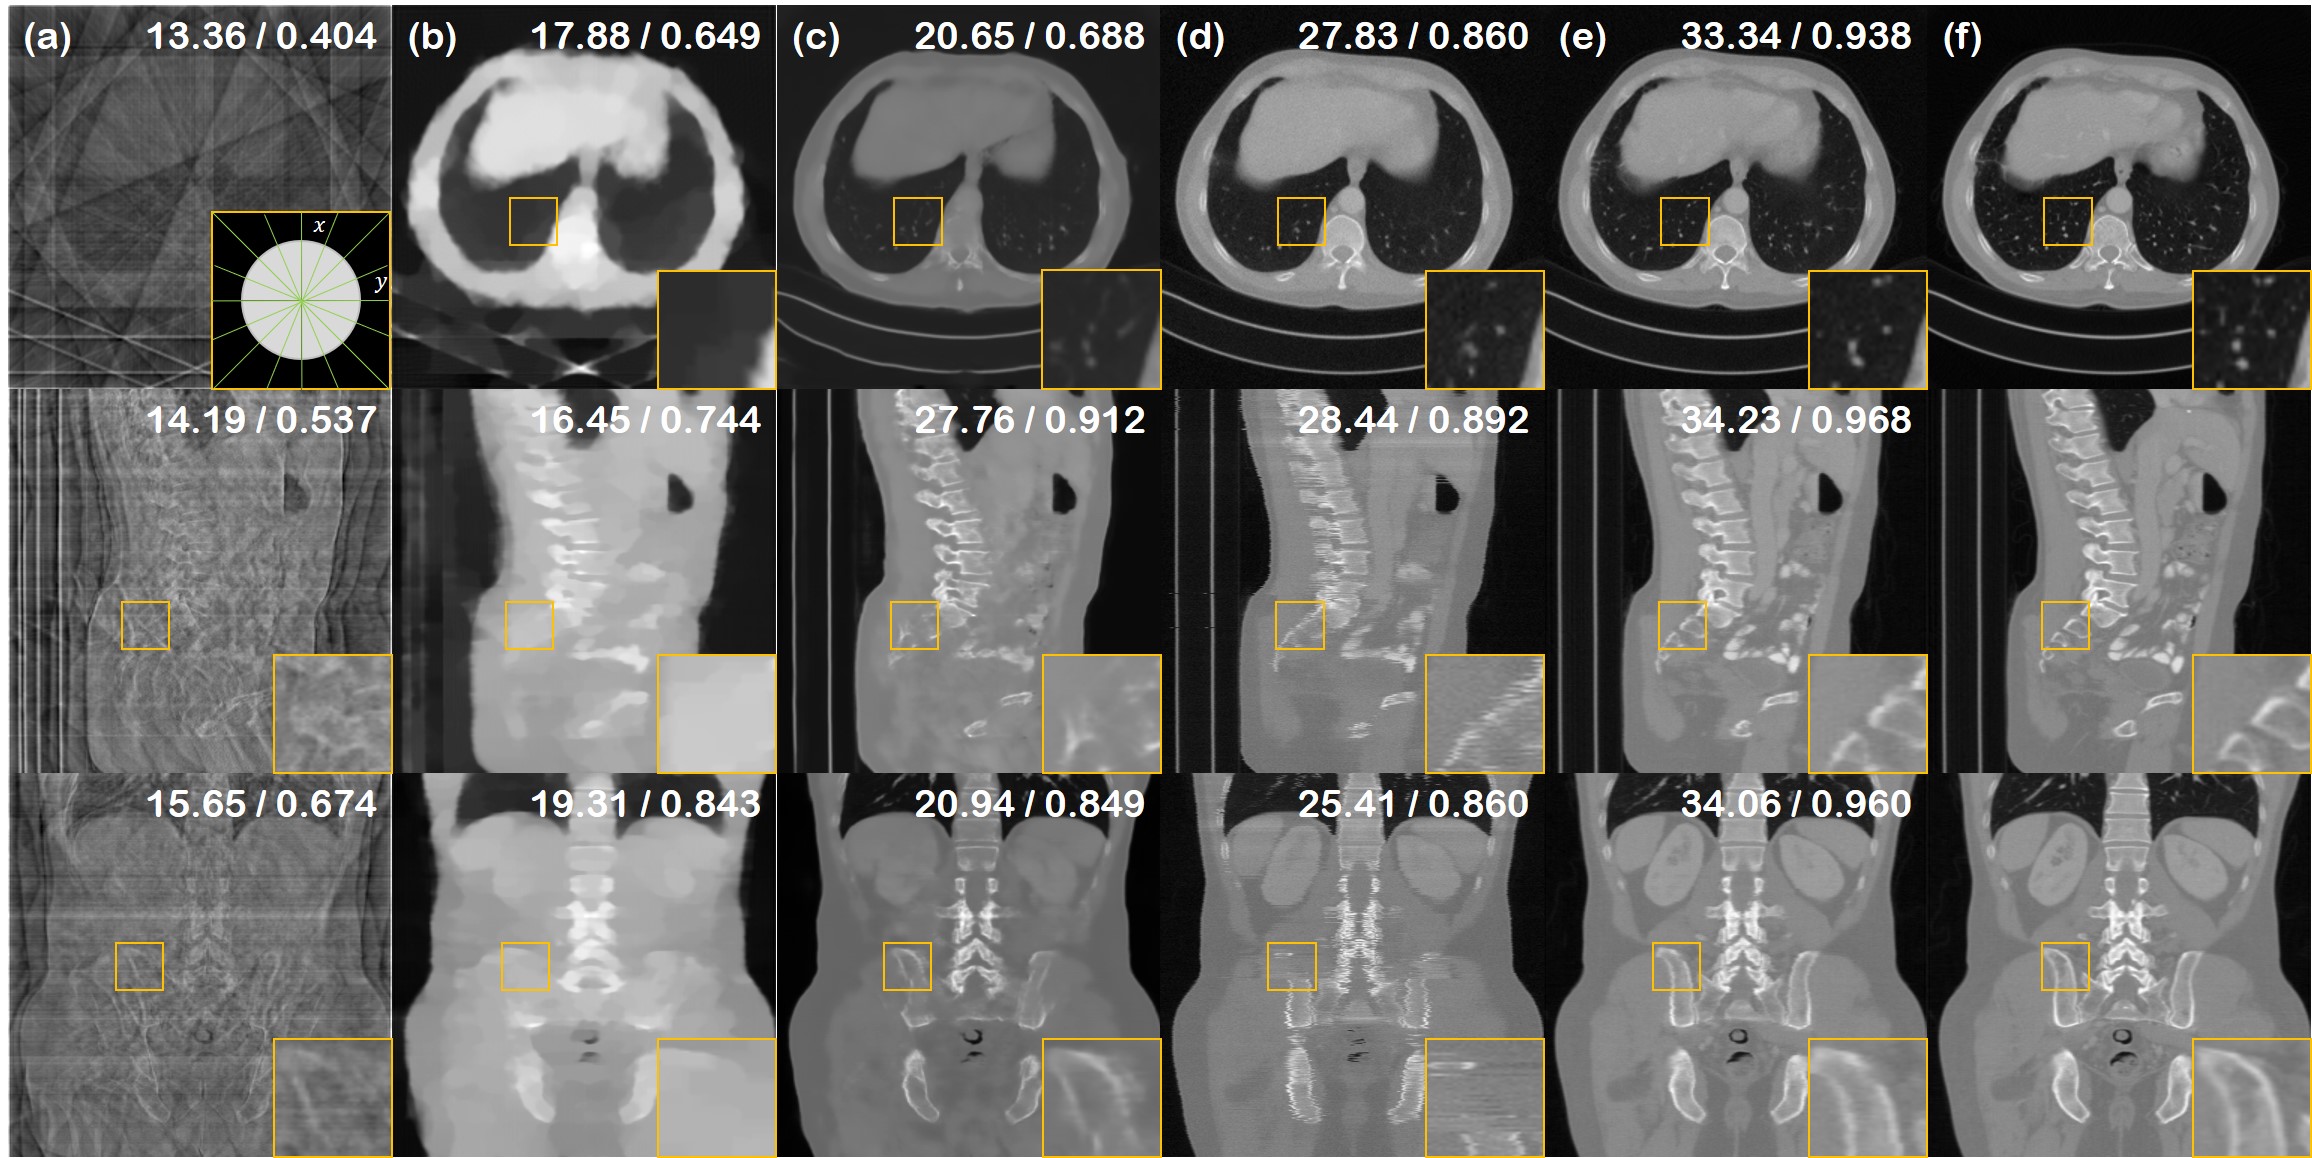

Figure 3: 8-view SV-CT reconstruction results of the test data (First row: axial slice, second row: sagittal slice, third row: coronal slice). (a) FBP, (b) ADMM-TV, (c) Lahiri et al. [16], (d) Chung et al. [5], (e) proposed method, (f) ground truth. PSNR/SSIM values presented in the upper right corner. Green lines in the inset of first row (a): measured angles.

Sparse-view CT. We present the quantitative metrics of the SV-CT reconstruction results in Table 1. The table shows that the proposed method outscores the baselines by large margins in most of the settings. Fig. 3 and Supplementary Fig. 6 show the 8,4-view SV-CT reconstruction result. As shown at the first row of each figure, axial slices of the proposed method have restored much finer details compared to the baselines. Furthermore, the results of sagittal and coronal slices in the second and third rows imply that DiffusionMBIR could maintain the structural connectivity of the original structures in all directions. In contrast, Chung et al. [5] performs well on reconstructing the axial slices, but do not have spatial integrity across the z𝑧z direction, leading to shaggy artifacts that can be clearly seen in coronal/sagittal slices. Lahiri et al. [16] often omits important details, and is not capable of reconstruction, especially when we only have 4 number of views. ADMM-TV hardly produces satisfactory results due to the extremely limited setting.